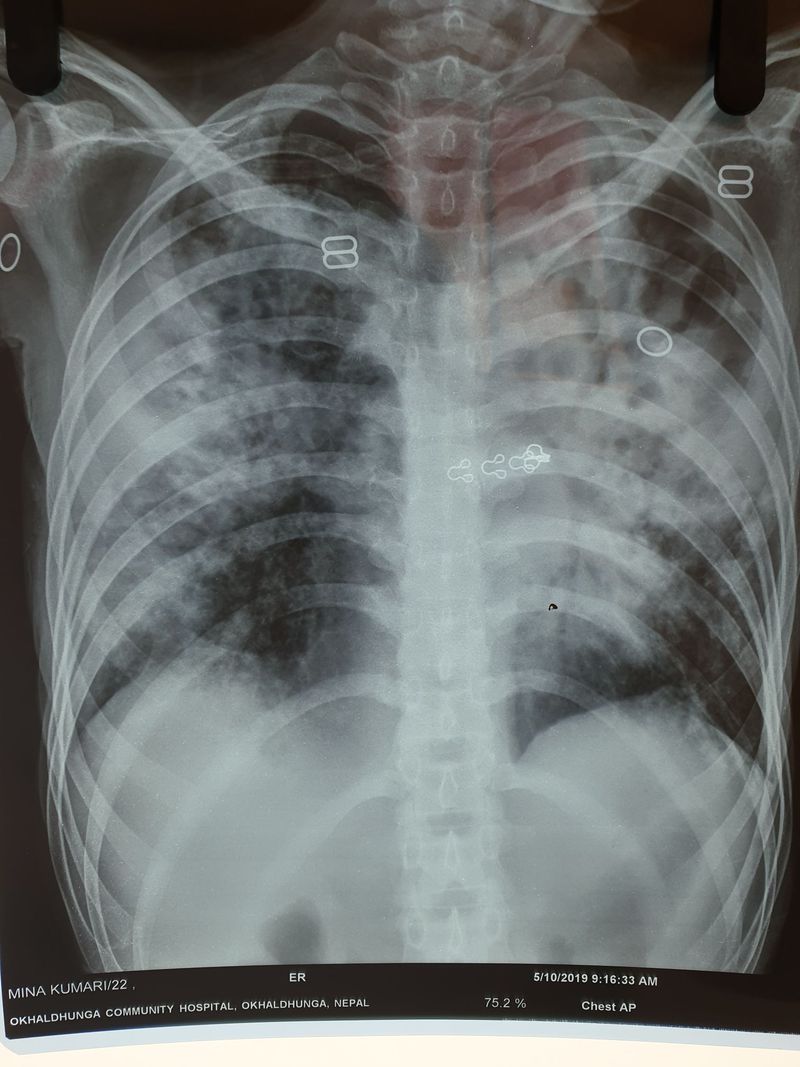

TB , metastasis ??????!!